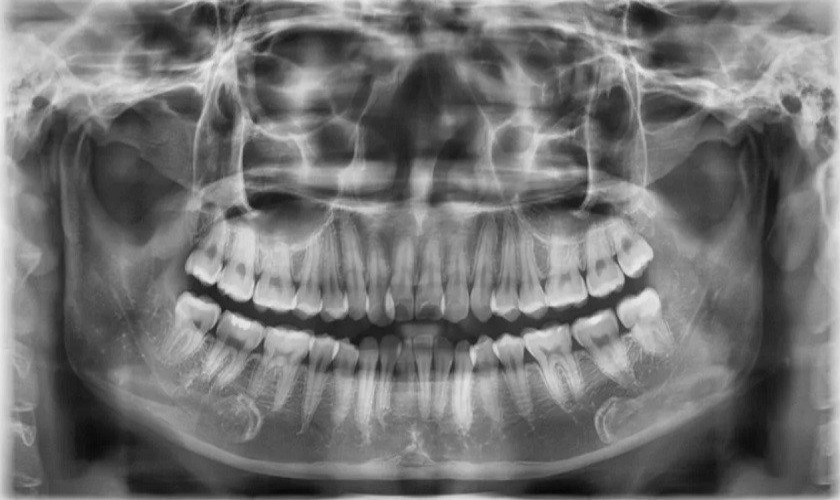

Vai trò của chụp X quang răng toàn cảnh

Vai trò của chụp X quang răng toàn cảnh cung cấp hình ảnh rõ nét, chính xác, phân giải cao về toàn bộ răng giúp bác sĩ chẩn đoánXem thêm